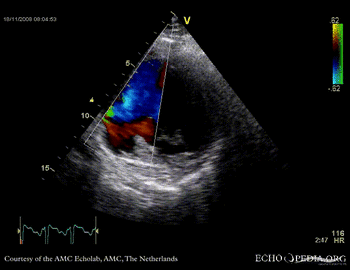

Rupture of the ventricular septum

VSR 4